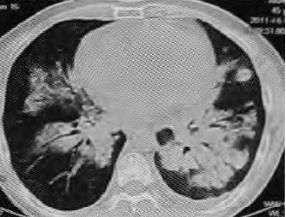

患者老年女性,高热,尿蛋白++,轻度贫血。抗感染治疗无效。

CT如下:

也是蝶羽征,沿着肺门基本对称分布。

P-ANCA阳性。

最终诊断:显微镜下多血管炎。